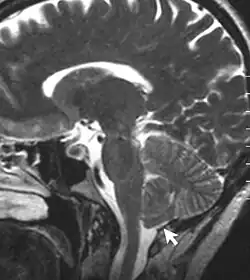

Chronic secondary headache or orofacial pain is a result of an underlying disorder.[24] Chronic secondary headache or orofacial pain can be caused by ischemic stroke, nontraumatic intracranial hemorrhage, arteritis, unruptured vascular malformation, pituitary apoplexy, genetic vasculopathy, increased cerebrospinal fluid pressure, Chiari malformation type I, intracranial neoplasms, epileptic seizure, substance withdrawal,[24] bacterial meningitis, meningoencephalitis, viral meningitis or encephalitis, brain abscess, intracranial fungal or other parasitic infections, hypoxia, hypercapnia, dialysis, arterial hypertension, and hypothyroidism.[25]